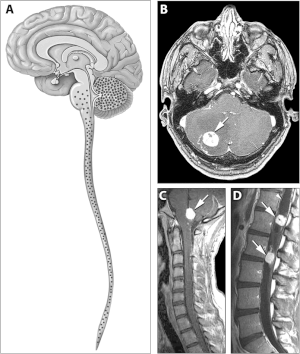

![]() | |

| Typical distribution of hemangioblastomas in Von Hippel–Lindau disease | |